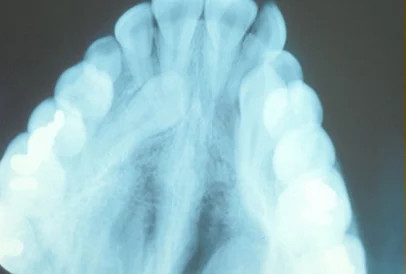

As you can see here, the treatment for impacted teeth gets more complicated as time goes on:

• 11-12 year olds: At this stage, we are able to preemptively make space for the canines, ensuring a good chance for successful eruption.

• 13-14 year olds: Even if we clear space for the canines, they will likely need to be “pulled down” into place with braces.

• 15 years +: As time goes on, the impacted tooth will fuse into position and the only remedy will be extraction and restoration.

• Complications of untreated impacted teeth include the loss of neighboring tooth roots and cystic lesions.